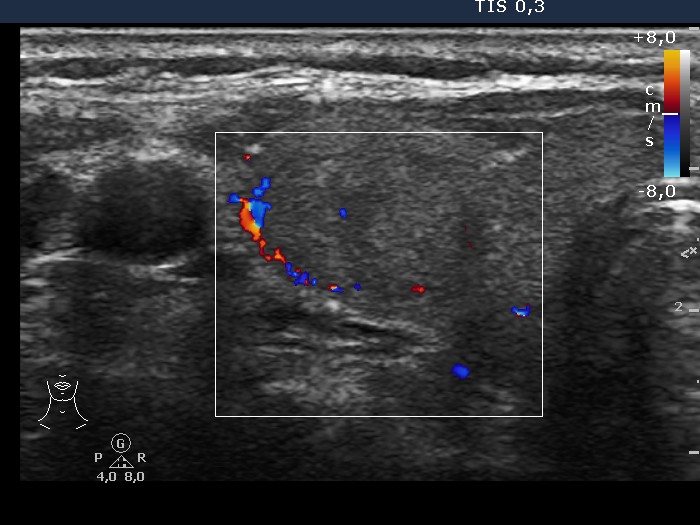

Ultrasonography: the thyroids were echonormal. There was a moderately hypoechogenic nodule displaying a halo sign and perinodular blood flow in the right lobe .